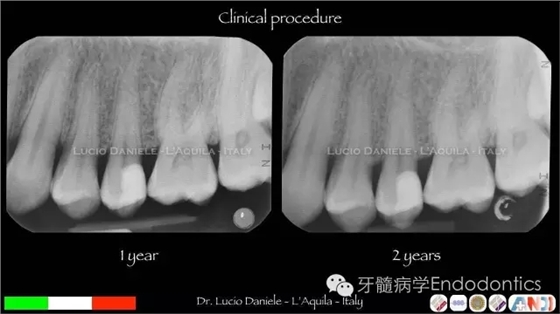

圖27.術后1年、2年隨訪